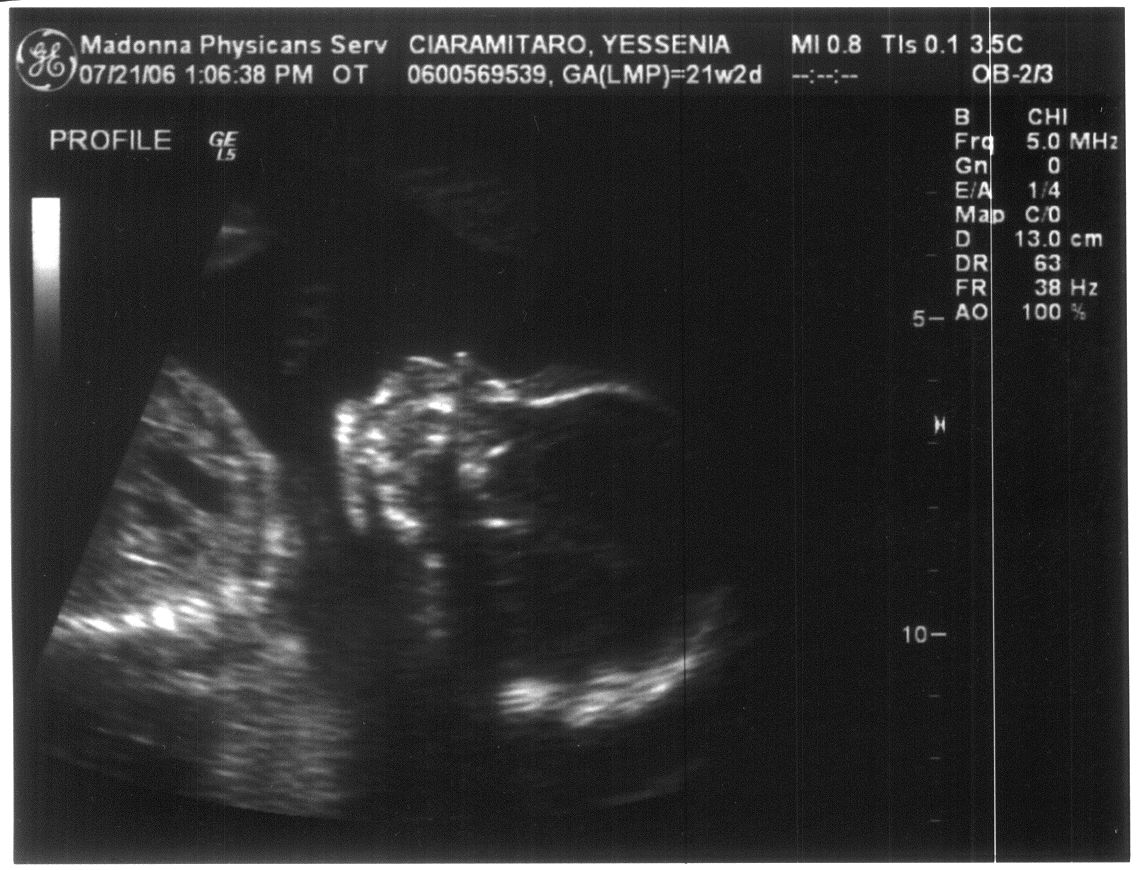

Last Modified On:March 2, 2015 5 PM Welcome to the future member of the Ciaramitaro clan!

Looks like our baby is coming bundled with a Skeleton Halloween Costume!